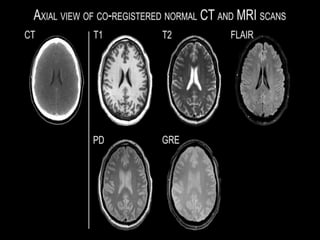

Basic Sequences

T1 to view anatomy

T2 to detect a pathologic process

(edema, swelling)

Proton Density (PD)

great for ligamentous anatomy

Basic Pulse Sequences for MRI Imaging

Image type Fat Water Advantage

T1 Bright Dark Anatomical detail

T2 Intermediate Bright ++ edema

Fat

Suppressed

T2

Very Dark Very Bright ++++ edema

T1 • Low TR(400-700 msec) • Low TE (20-40 msec) T2 • High TR (2,000-3,000 msec) • High TE (40-70 msec) Proton density • High TR (2,000-3,000msec) • Low TE (20-40 msec)

Basic Sequences T1 toview anatomy T2 to detect a pathologic process (edema, swelling) Proton Density (PD) great for ligamentous anatomy

Basic Pulse Sequencesfor MRI Imaging Image type Fat Water Advantage T1 Bright Dark Anatomical detail T2 Intermediate Bright ++ edema Fat Suppressed T2 Very Dark Very Bright ++++ edema